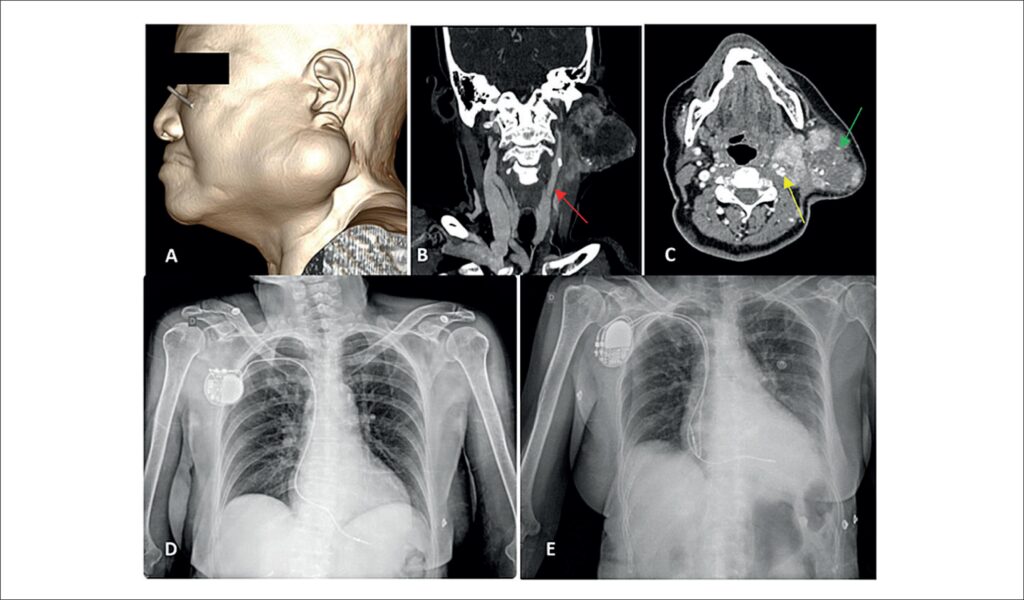

Carotid Sinus Syndrome Associated with Carcinoma Ex-Pleomorphic Adenoma: What Is the Role of Artificial Cardiac Stimulation?

Carotid sinus syndrome (CSS) is defined as syncope or pre-syncope associated with at least 3 seconds of asystole (cardioinhibitory response) and/or a drop of at least 50 mmHg in arterial systolic blood pressure (vasodepressor response) in response to stimulation of the carotid sinus. First recognized by Weiss and Baker in 1933, there have been since then reports of the association between neck masses and the occurrence of syncope. Among its causes is carcinoma ex-pleomorphic adenoma (CXAP), a rare malignant neoplasm that develops from a primary or recurrent pleomorphic adenoma. It represents 3.6% of all salivary gland neoplasms and 11.6% of all malignant neoplasms of these glands. CSS caused by neck masses is due to compression and invasion of the carotid sinus and nerve branches. This syndrome has 3 subtypes: cardioinhibitory, vasodepressor, and the mixed type. A fourth type of “cerebral response” has been previously described in the literature, in which direct compression of the carotid artery causes ipsilateral cerebral ischemia leading to seizures.